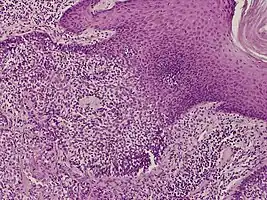

They are described as < 1 to 2 cm, pink/red shiny, exophytic lesions that can be pigmented and are clinically very similar to pyogenic granulomas.[3] Histologically, the cells as PAS-positive and clearly surrounded by normal keratinocytes. These tumors are surgically excised usually without complication or recurrence, although malignant porocarcinomas can recur and metastasize to local lymph nodes.[5]

Dermoscopy and histopathology of eccrine poroma: (A) Clinical presentation of a nonpigmented eccrine poroma sensu stricto as a pink nodule located on the foot (B,C) Dermoscopy shows milky red areas (light blue arrow), milky red globules (dark blue triangle), and dotted vessels (black arrow) (original magnifications ×20 and ×40, respectively). (D,E) Histopathologically, the neoplasm consists of poroid and cuticular cells and tubular structures that are continuous with the epidermis (H&E stain, original magnifications ×10 and ×40, respectively).[6]